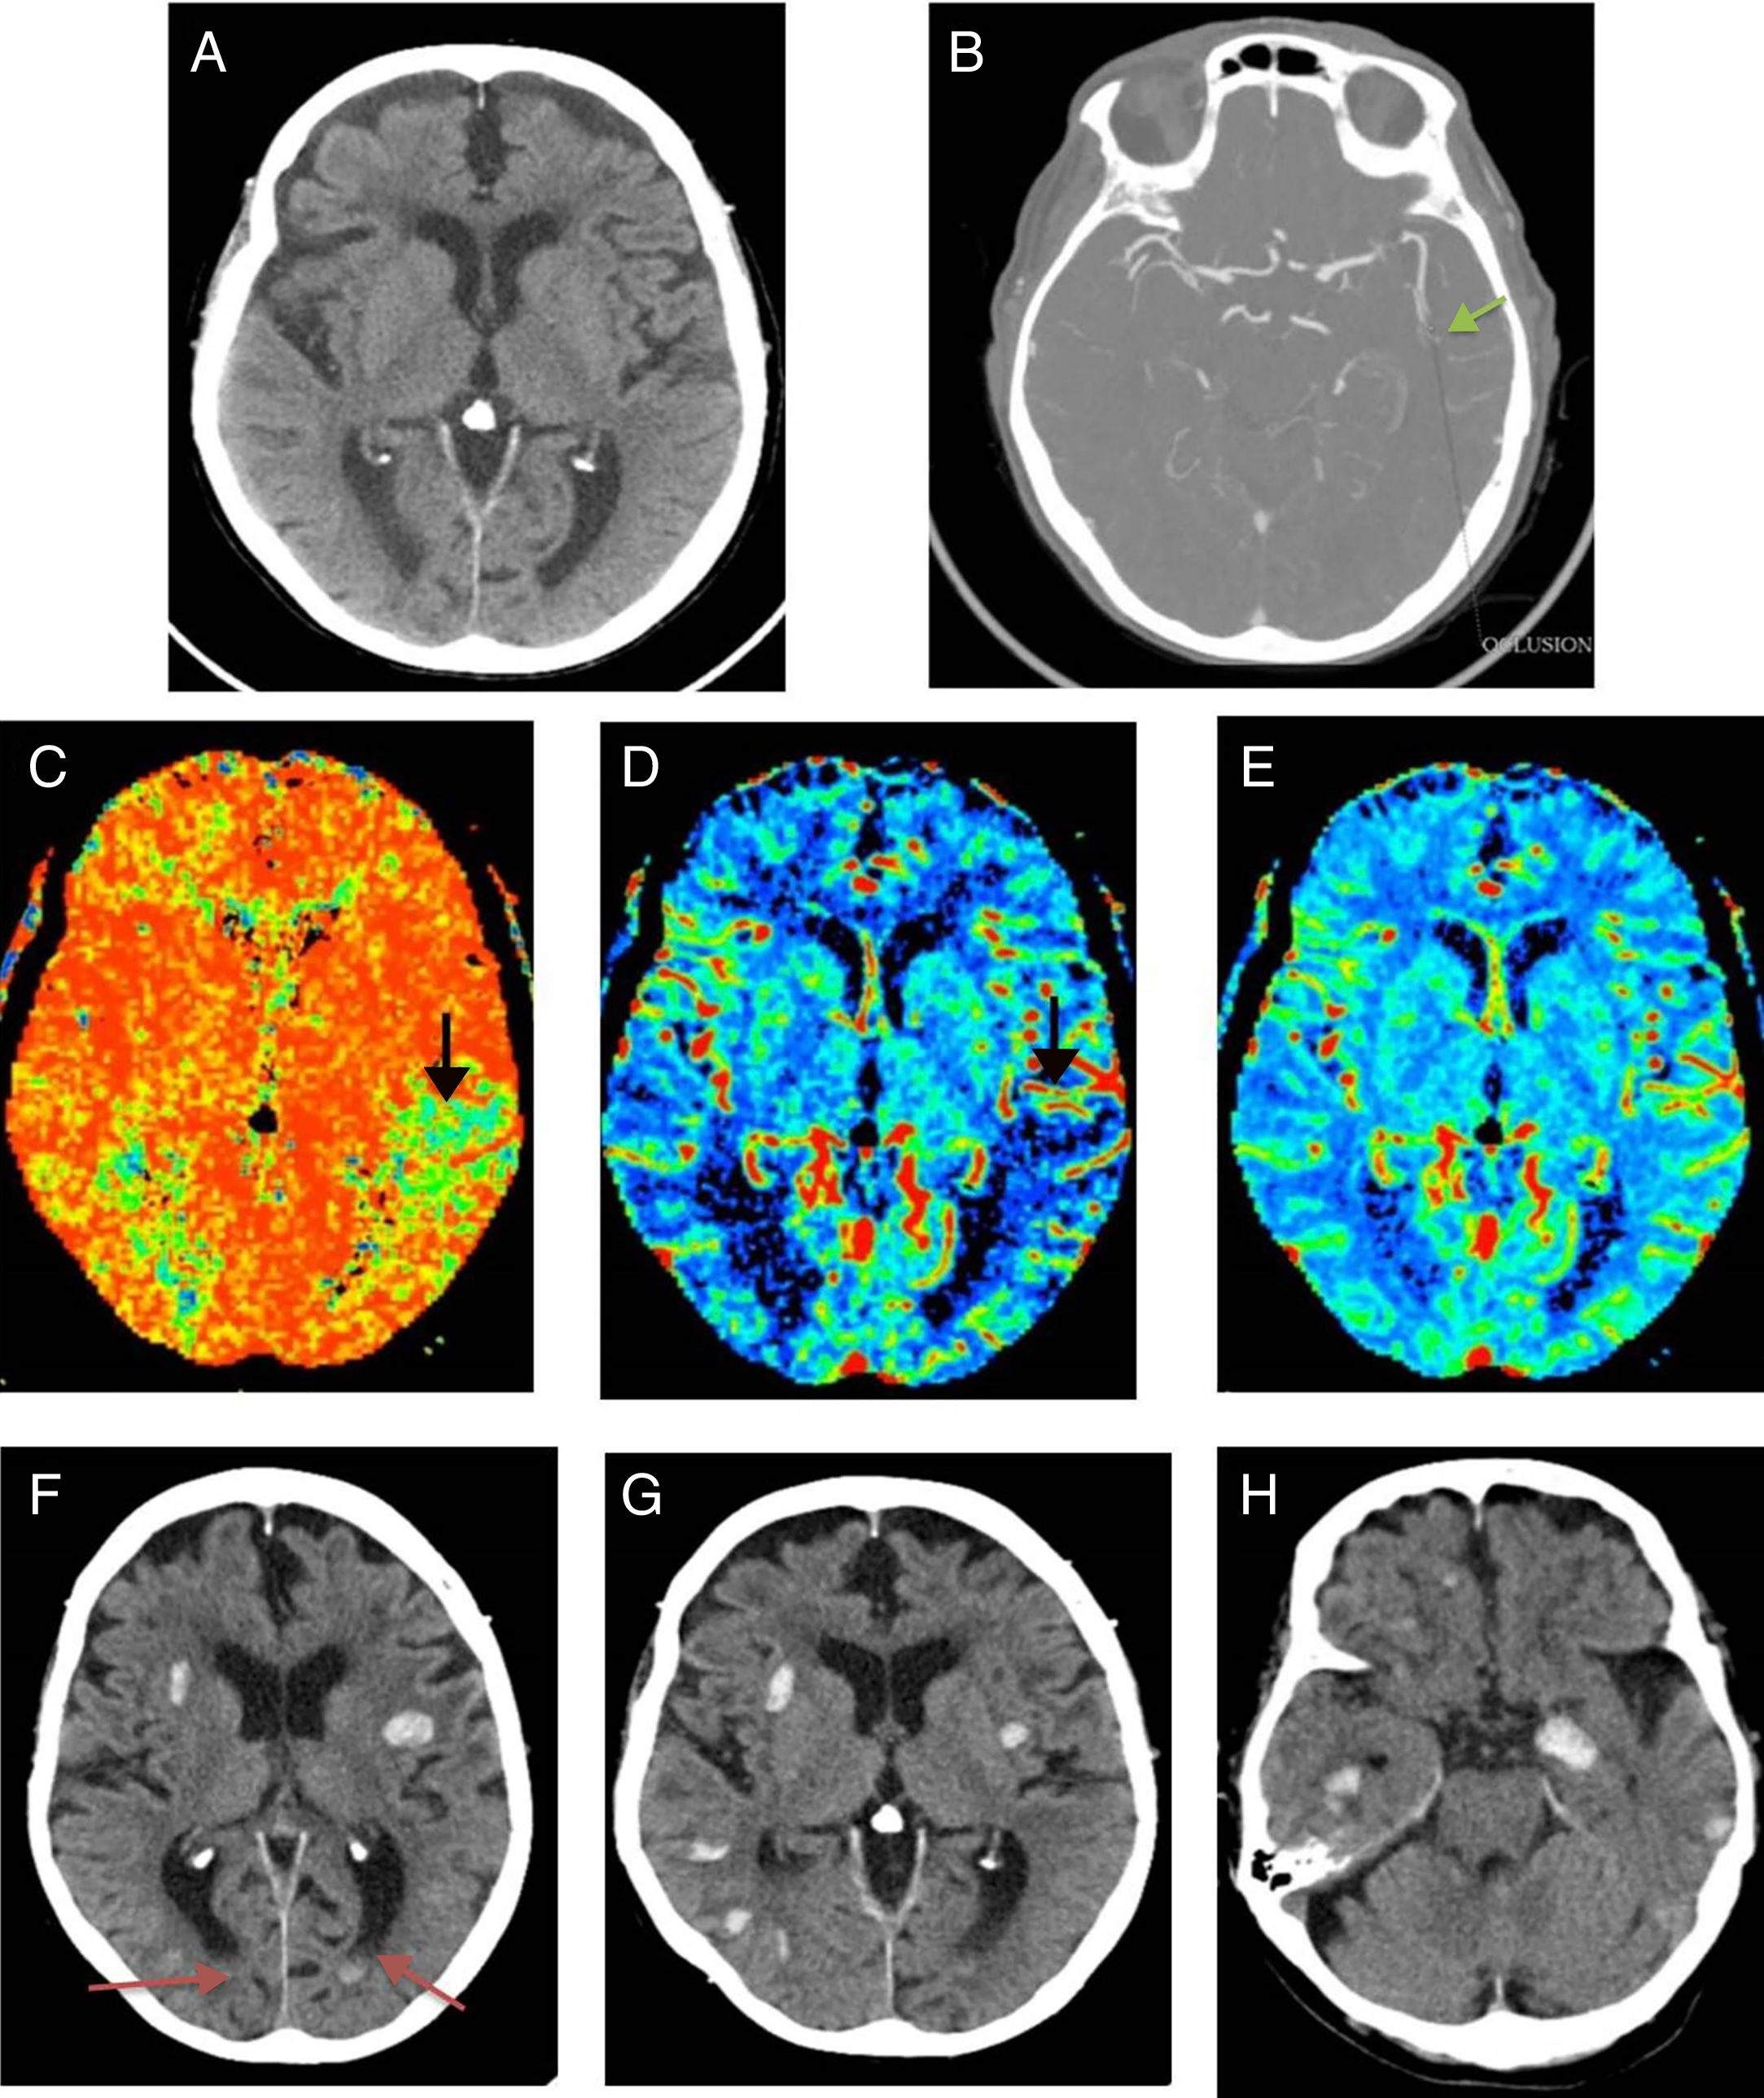

Presentamos el caso de una mujer de 90 años con antecedentes de accidente isquémico transitorio carotídeo izquierdo y estenosis aórtica leve. Acudió a urgencias con afasia motora de inicio desconocido. En la exploración física se obtuvo un NIHSS 5. Se activó el Código Ictus y se realizaron tomografía computarizada (TC) cerebral, TC de perfusión cerebral y angio-TC de troncos supraaórticos-polígono de Willis, que pusieron de manifiesto un estudio basal con ASPECTS 10, un área de penumbra isquémica en el territorio de la arteria cerebral media izquierda y un trombo en el segmento M2 distal ipsilateral (fig. 1 A-E). A pesar de la edad avanzada de la paciente, dada la buena calidad de vida previa y los hallazgos de las pruebas de imagen, se inició terapia fibrinolítica. Pasadas 24 horas postratamiento, la paciente mostró mayor deterioro neurológico. Se solicitó una TC cerebral de control donde se visualizaron múltiples focos de sangrado intraparenquimatosos lobares y difusos (fig. 1 F-H). La distribución de los focos hemorrágicos, alejados del territorio afectado por el área de penumbra, descartó una transformación hemorrágica. Ante la sospecha de angiopatía amiloide (AA) se solicitó una resonancia magnética (RM) cerebral como prueba complementaria. Con base en los criterios de Boston, la RM apoyó el diagnóstico de “probable” AA, al demostrar múltiples focos de sangrados antiguos visibles en la secuencia eco de gradiente T2 (fig. 2). Al alta, la paciente mantenía un cuadro de disfasia mixta.

A-E) Estudios pretratamiento. Tomografía computarizada (TC) de cerebro sin contraste intravenoso (A), angio-TC-polígono de Willis (B) y estudio de perfusión cerebral (C-E) realizados a la paciente ante la sospecha de ictus isquémico. A) En la TC basal no se observan signos de isquemia aguda (ASPECTS 10). B) En la angio-TC-polígono de Willis se identifica un stop en segmento M2 izquierdo sugestivo de la presencia de trombo. C) Aumento del tiempo de tránsito medio (flecha) visible en los mapas de perfusión. D) disminución del flujo sanguíneo (flecha). E) volumen normal, sin variación en el estudio de perfusión. Las alteraciones mencionadas se localizan en la región parietal izquierda, territorio de la arteria cerebral media izquierda, y son sugestivas de penumbra. F-H) TC cerebral sin contraste, cortes axiales, realizada 24 horas tras el inicio del tratamiento fibrinolítico. Se identifican múltiples focos de sangrado, bilaterales, alejados del área de isquemia, de distribución difusa cortical, lobar y de predominio supratentorial. Núcleos grises profundos respetados. La semiología radiológica de los hallazgos descritos es sugestiva de angiopatía amiloide. Niveles hemáticos en astas ventriculares occipitales izquierdas (flechas en panel F).

La transformación hemorrágica de un área isquémica cerebral es una complicación frecuente tras el tratamiento fibrinolítico, presente en el 5,8%1 de los casos. Los principales factores de riesgo son la edad avanzada, la hipertensión arterial y el bajo peso corporal. Sin embargo, existe una complicación menos discutida, que aumenta la morbilidad de estos pacientes. Se trata de la hemorragia intracraneal alejada del área isquémica o remota (HICr)2. Este tipo de complicación es vista con un porcentaje del 1,3-3,7%3. Estudios realizados proponen dos posibles asociaciones que podrían explicar la causa subyacente a este tipo de sangrado según la localización. La primera se establece entre la hemorragia de localización profunda con la hipertensión arterial y la segunda entre el sangrado lobar con microsangrados previos que actuarían como marcadores de patología de pequeño vaso subyacente (AA)3.

La AA se debe al acúmulo de la proteína β amiloide en pequeños y medianos vasos, lo que condiciona mayor fragilidad vascular. El envejecimiento constituye el principal factor de riesgo, y es más frecuente en personas de edad avanzada4, las cuales presentan mayor incidencia de patología isquémica cerebral. La principal manifestación radiológica de esta entidad (AA) considerada en los criterios de Boston es la presencia de hemorragias agudas/crónicas de distribución cortical y/o corticosubcortical4. El diagnóstico diferencial debe plantearse con otras patologías que pueden causar sangrado cerebral, como hipertensión arterial, malformaciones cavernomatosas múltiples y traumatismos cerebrales previos. Por tanto, debe realizarse un diagnóstico de exclusión, y es importante tener presente que la característica distribución con respeto de los núcleos grises profundos y el tronco del encéfalo permite distinguirla de la hemorragia secundaria a la hipertensión arterial4.